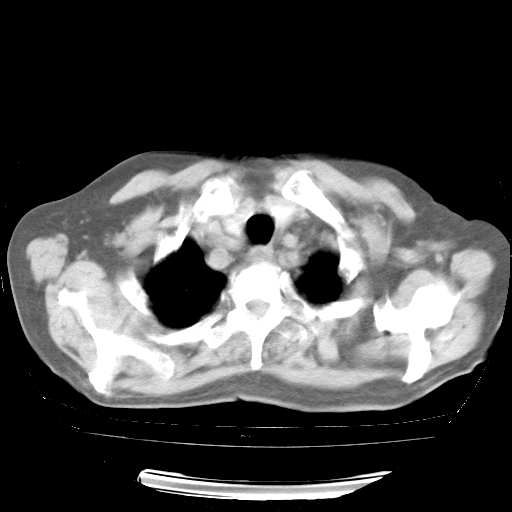

4月28日肺部CT——再次出现类似去年5月9日——透光度降低,“间质性”改变。

4月28日肺部CT